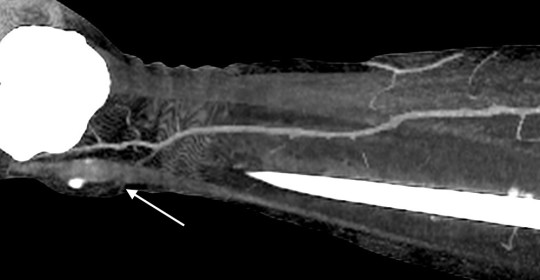

Пацієнти та методи. Відповідно до мети роботи було проаналізовано дані обстеження 46 пацієнтів, що знаходилися на стаціонарному лікуванні в опіковому відділенні КЗ «Дніпропетровська міська клінічна лікарня №2 ДОР» з глибокими локалальними ушкодженнями нижніх кінцівок в період з 2009 по 2015 рік, і яким було виконано 54 оперативних втручань із використанням локальних перфорантних клаптів з живлячою ніжкою, що включала одну домінантну перфорантну артерію. Пацієнти були розділені на дві групи. В групу 1 (контрольну) було включено 25 пацієнтів (29 оперативних втручань) у яких стандартне обстеження включало локацію перфорантів за допомогою аудіо-доплера «Мінідоп» з датчиком 8 MHz. Передбачуване місце вихода перфоранта та його напрямок позначалися на шкірі пацієнта за допомогою маркера [10,12]. (Мал. 1). В групу 2 було включено 21 пацієнта (25 оперативних втручань) у яких стандартне передопераційне обстеження було модифіковане за рахунок контрасної КТ-ангіографії [8,7] з обробкою візуальних карт судинної системи в зоні втручання програмою ”Osirix” (Мал. 2).

Мал. 2. Контрасна КТ-ангіографія з обробкою візуальної карти судинної системи нижньої кінцівки в зоні втручання програмою ”Osirix”. Точку виходу перфрантної артерії в шкіру над кісточкою – відзначено стрілкою.